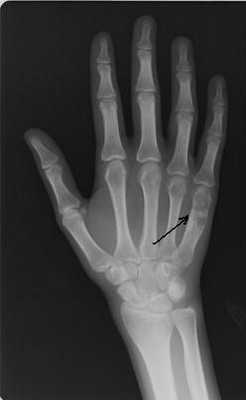

Для эндохондромы в области коротких трубчатых костей (кисти, стопы) характерно ограниченное гомогенное просветление, которое зачастую занимает весь поперечник кости. На рентгенограммах длинных трубчатых костей хондромы выглядят, как облаковидные просветления неправильной формы, иногда - с тенями обызвествления. Рентгенологическая картина хондромы в ряде случаев может напоминать однокамерную костную кисту, локализованный очаг фиброзной дисплазии и гигантоклеточную кистозную опухоль. Необходимо также исключить признаки озлокачествления хондромы. Для уточнения диагноза выполняют биопсию с последующим гистологическим исследованием материала.

Диагностика энхондром, как правило, несложна. На рентгенограммах длинных трубчатых костей выявляется центрально расположенное облаковидное просветление. В зоне просветления могут обнаруживаться более темные участки - очаги кальцификации. Опухоли в области коротких трубчатых костей обычно выглядят однородными и занимают большую часть поперечника или весь поперечник кости. Кортикальный слой не нарушен. На КТ кости определяется аналогичная картина, преимуществом компьютерной томографии является возможность более подробно рассмотреть структуру энхондромы.